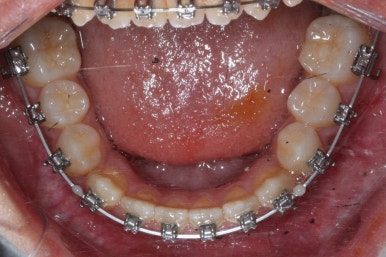

위 사진들은 부산주걱턱교정 키다리아저씨치과에 내원하셨을 당시의 입안 모습입니다.

입 안의 모습에서도 주걱턱의 특징으로는

하악이 앞으로 나와있습니다.

윗니는 뻐드러지고 아래 앞니는 뒤쪽으로 쓰러져 있습니다.

교합이 맞지 않습니다.